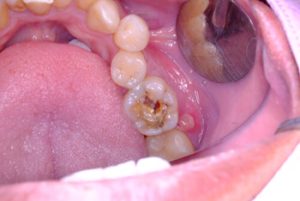

Tooth decay, also called dental caries, begins when harmful bacteria in the mouth produce acid that slowly breaks down the tooth enamel, which is the strong and protective outer layer of your teeth. These bacteria thrive on sugary foods, and without good oral hygiene, they create a sticky film called plaque. As plaque builds up, it eats away at the tooth’s structure, leading to small holes called cavities.

Once a cavity forms, it doesn’t get better on its own. Left untreated, it can result in infection, gum disease, or even require treatments like root canals. Worse still, tooth decay can spread, affecting other areas of your mouth and potentially the mouths of others.

Tooth decay is caused by cavity causing bacteria, particularly Streptococcus mutans, which feed on sugar and produce acid as a byproduct. These bacteria aren’t just confined to one tooth. Once established in the mouth, they can migrate, creating new tooth cavities on neighbouring teeth, especially if oral hygiene is poor or decay is left untreated.

Once a tooth is affected, the bacteria that cause cavities can thrive and reproduce, affecting nearby teeth and damaging more of your tooth enamel.